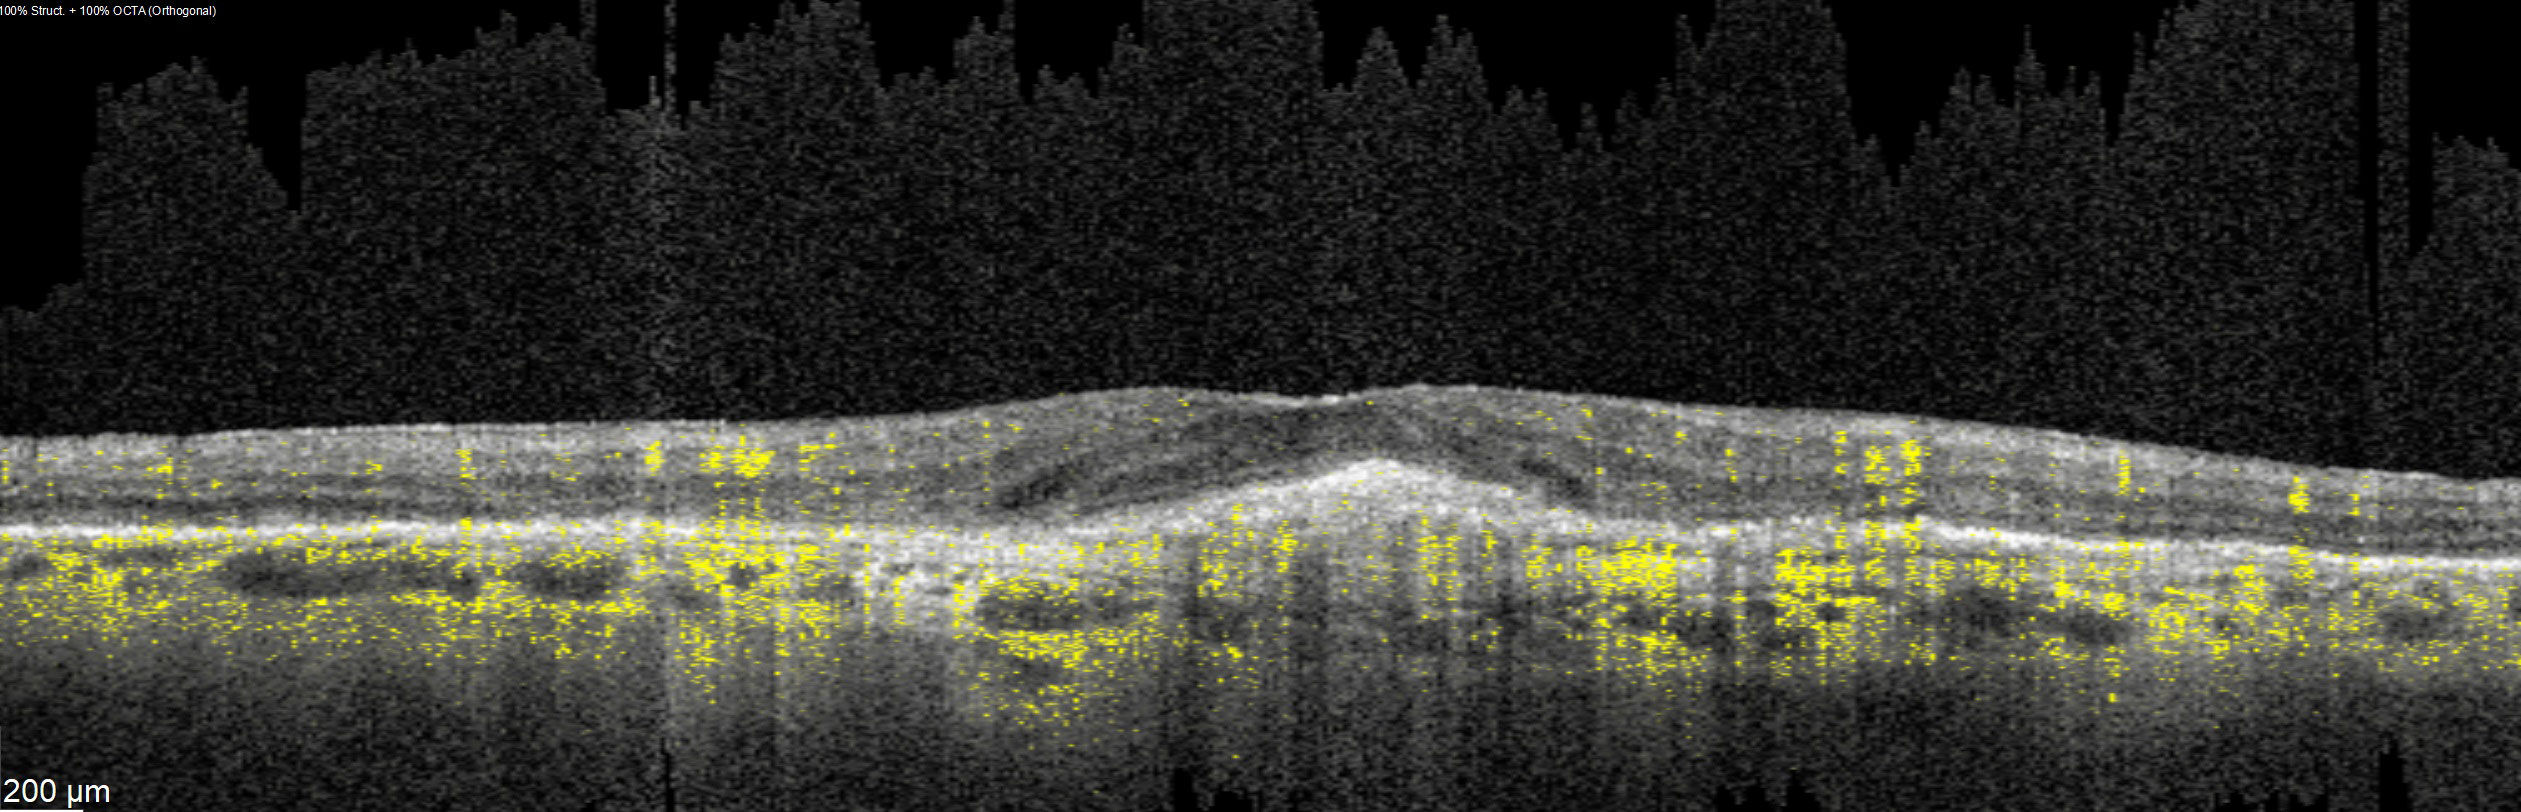

Offering the ideal speed-quality ratio for OCTA, 125 kHz allows you to increase your throughput without any clinically relevant loss in image quality in comparison to the current 85 kHz scan speed. The fast acquisition of images allows for visualization of flow, even in miniscule vessels, while minimizing artefacts, resulting in sharp and detailed images of the capillary network. Additionally, you can decrease chair time when you speed up acquisition with the Glaucoma Module Premium Edition in your glaucoma workflow, if applicable.

SPECTRALIS with SHIFT technology and 125 kHz scan speed empowers you to offer customized diagnostic OCTA imaging of both the retina and the optic nerve head to meet the needs of each individual patient – or adjust to 85 kHz if your patient’s condition requires longer light exposure.

125 kHz – A fast scan speed for improved workflow and high OCTA image quality.